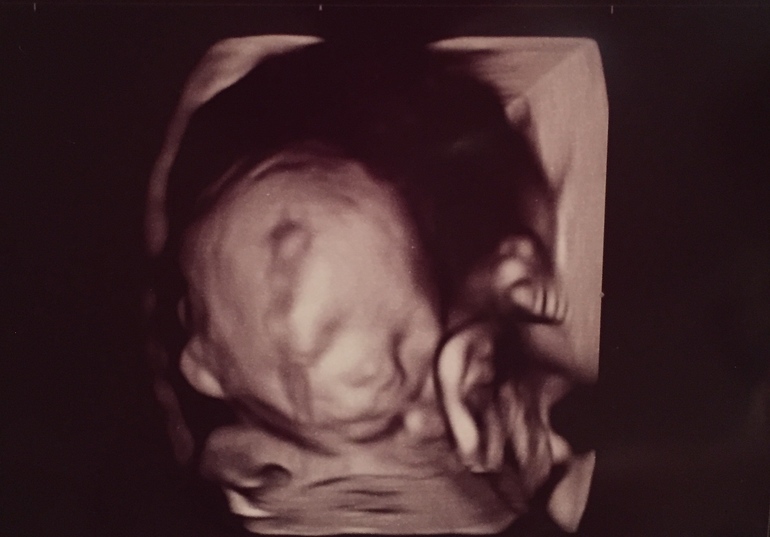

Свидание состоялось! Моя интуиция меня не подвела. С самого первого дня я чувствовала, что это девочка ❤️

Весим уже 324г😊